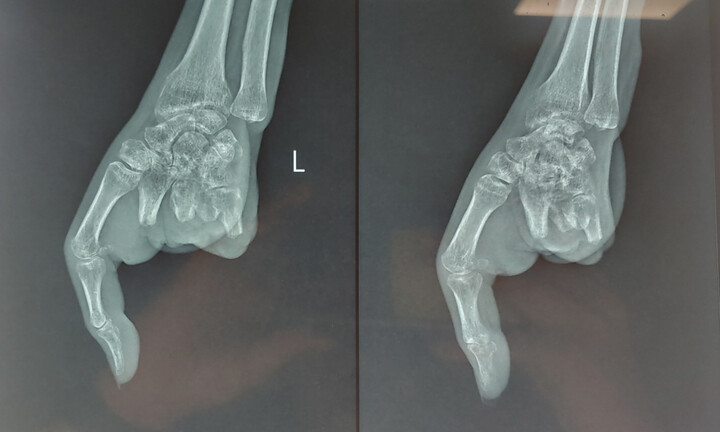

Theo thông tin từ Bệnh viện Đa khoa Hùng Vương (Phú Thọ), Trung tâm Cấp cứu 115 Hùng Vương vừa cấp cứu cho trường hợp bệnh nhi 14 tuổi trong tình trạng đau đớn, phù nề, chảy dịch nước, biến dạng khuôn mặt, da mặt dính bẩn của lá cây. Hai bàn tay và cổ tay của bệnh nhi cũng xuất hiện nhiều vết phồng rộp, chảy dịch.

Qua khai thác thông tin từ người nhà, bệnh nhi này bị bỏng từ một ngày trước. Tuy nhiên, trẻ không được đưa tới bệnh viện ngay mà đắp lá chữa bỏng tại nhà.

Sau một ngày, mắt của bệnh nhi sưng nề, không mở được và cảm giác đau đớn, gia đình mới đưa con tới bệnh viện cấp cứu. Hiện trẻ tiếp tục được tích cực cấp cứu và giảm đau.